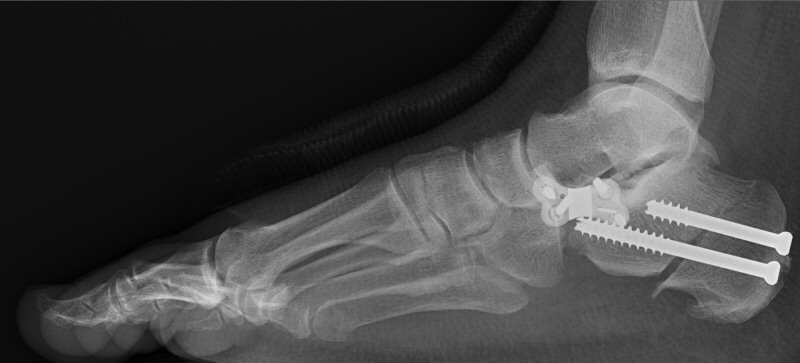

Plattfot opererad med kalkaneusosteotomi och Evans osteotomi